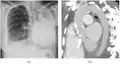

Extensive left-sided fibrothorax

Chest radiograph displaying inhomogeneous opacification of the left half of the chest that is fibrothorax

Autopsy specimen showing extensive pleural fibrosis

A fibrothorax can typically be diagnosed by taking an appropriate medical history in combination with the use of appropriate imaging techniques such as a plain chest X-ray or CT scan.[3] These imaging techniques can detect fibrothorax and pleural thickening that surround the lungs.[7] The presence of a thickened peel with or without calcification are common features of fibrothorax when imaged.[3] CT scans can more readily differentiate whether pleural thickening is due to extra fat deposition or true pleural thickening than X-rays.[3]

If a fibrothorax is severe, the thickening may restrict the lung on the affected side causing a loss of lung volume.[7] Additionally, the mediastinum may be physically shifted toward the affected side.[3] A reduction in the size of one side of the chest (hemithorax) on an X-ray or CT scan of the chest suggests chronic scarring.[6] Signs of the underlying disease causing the fibrothorax are also occasionally seen on the X-ray.[6] A CT scan may show features similar to those seen on a plain X-ray.[7] Lung function testing typically demonstrates findings consistent with restrictive lung disease.[6]